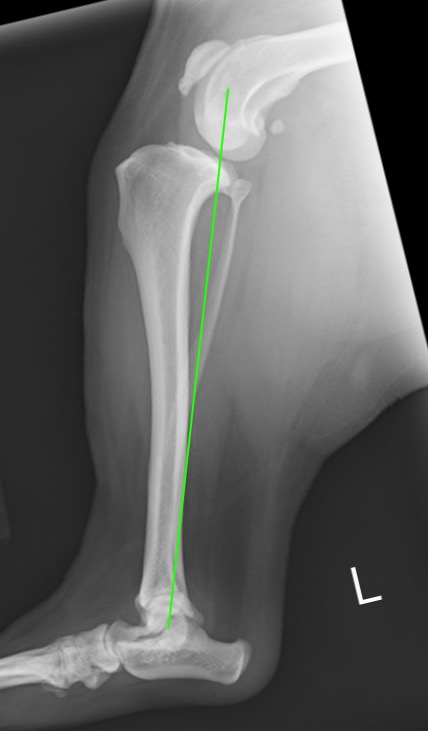

正常な足。大腿骨と脛骨の機能軸が直線状に並んでいる。

前十字靭帯を損傷した足。大腿骨と脛骨がずれてしまい体重がかけられない。